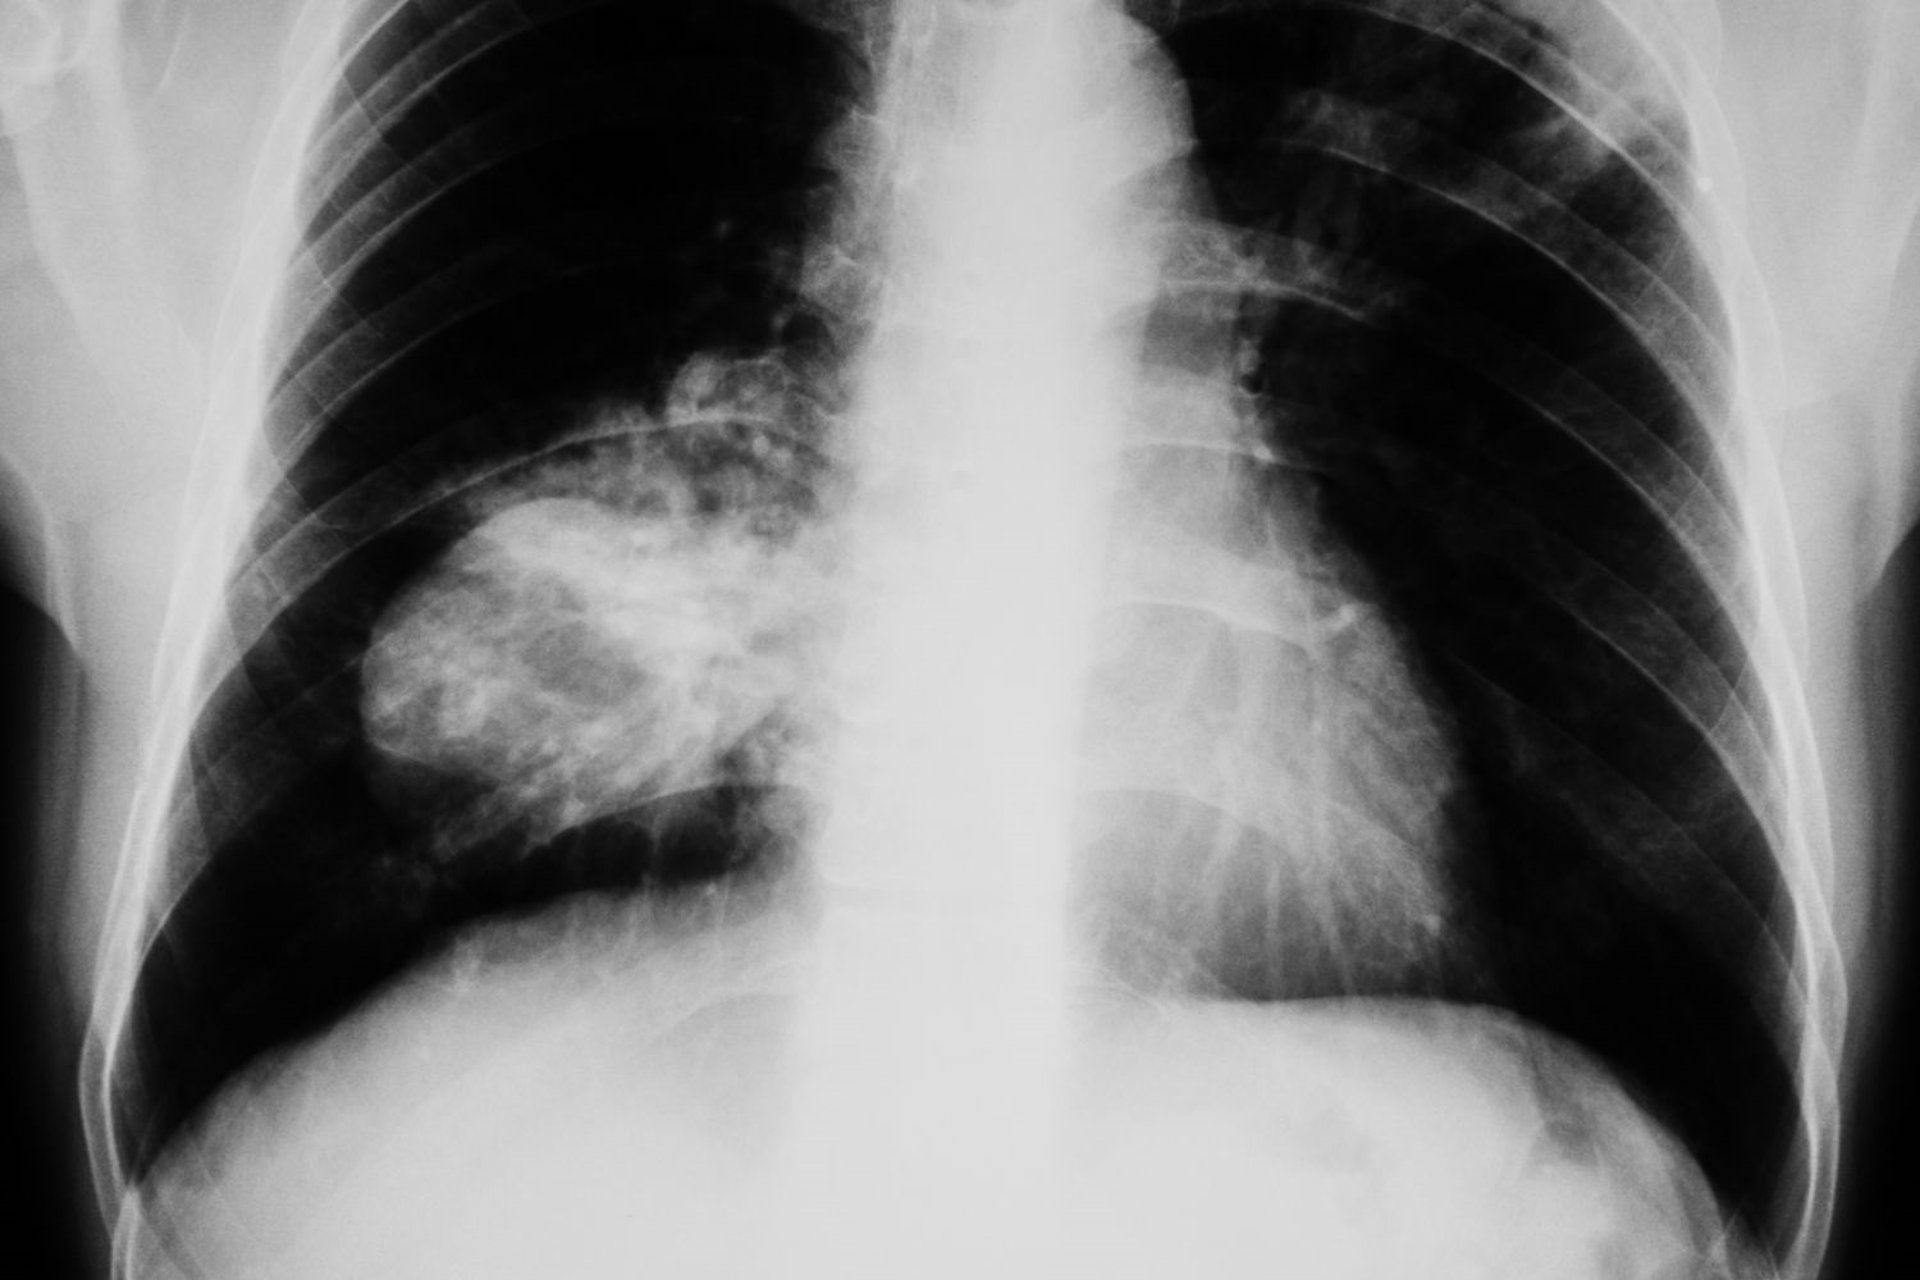

La doctora Dolores Isla, presidenta de ICAPEM y jefa de Oncología Médica en el Hospital Lozano Blesa, ha destacado la necesidad de mejorar la detección temprana del cáncer de pulmón en mujeres. Este llamamiento se realizó durante un evento coorganizado por ICAPEM y la Asociación Española de Afectados por Cáncer de Pulmón (AEACaP), con apoyo de la Fundación PharmaMar.

“El cáncer de pulmón de célula pequeña sigue siendo uno de los grandes retos clínicos. En el caso de las mujeres, su abordaje requiere un análisis más profundo, ya que pueden existir diferencias en sus factores de riesgo, características clínicas, evolución y respuesta a los tratamientos”, apuntó la doctora Isla.

El cáncer de pulmón de célula pequeña en mujeres, que representa el 15% de los diagnósticos de este tipo de cáncer, es especialmente agresivo y ha visto un incremento en su incidencia entre mujeres recientemente. Durante el evento, se aprobó un Manifiesto que destaca los principales desafíos para las mujeres con este diagnóstico y sugiere acciones específicas para mejorar su cuidado.